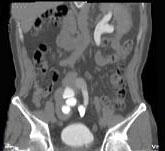

问题 男,65岁,反复发作的下腹部疼痛向会阴部放射伴血尿1 年余,CT如图所示,下列说法正确的是 ( )

选项 A、左侧输尿管扩张 B、考虑为先天性异位肾合并对侧输尿管下端结石 C、右肾窝内未见肾影,于盆腔入口处L~S水平见异位肾影 D、左侧输尿管在膀胱入口处可见一高密度结石影 E、左肾位置形态无异常